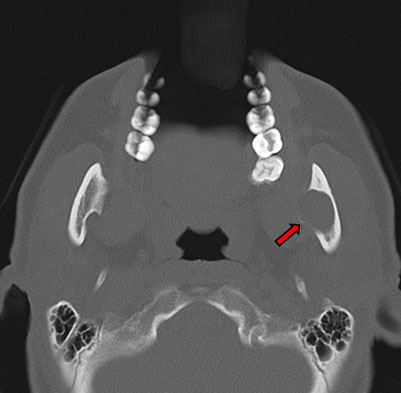

In August 2017, a 48-year-old Japanese woman visited the dental clinic because of occlusal pain in her left wisdom tooth. A panoramic X-ray showed an oval-shaped radiolucent area in the left mandibular ramus. She presented to our department for careful examination. Regarding the extraoral findings, no mass was palpable in the left mandible, and there was no dysesthesia in the left mental nerve area. Intraorally, no swelling or induration was observed inside the mandibular ramus, moreover, there was no difference between the two sides and the mucosa was a normal color. Her medical history included hyperlipidemia, iron-deficiency anemia, and diabetes. A panoramic X-ray revealed an almost circular and well-defined translucent image in the left mandibular ramus (Figure 1). Computed tomography (CT) revealed bone depression in the left mandibular ramus, and more thinning bone was seen inside. There was no obvious abnormal bone destruction. The internal density was similar to that of adipose tissue (Figure 2). Magnetic resonance imaging (MRI) revealed a lesion measuring 18×17×21 mm in size with mixed moderate and high signal intensity on fat-suppressed T2-weighted imaging in the left mandibular ramus. Gadolinium contrast-enhanced T1-weighted imaging showed no clear enhancement. Based on the clinical and imaging findings, it was likely to be a cystic lesion (Figure 3). Considering the anatomical site (it was located inside the mandibular ramus), we decided not to perform biopsy.

Figure 2: Computed tomography (axial plane). A bone defect can be seen in the left mandibular ramus, and more thinning bone can be seen inside (arrow).